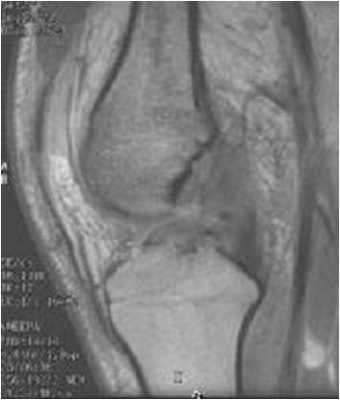

МРТ коленного сустава. Т1-взвешенная сагиттальная МРТ. Крестообразные связки в норме.

ЗКС, как видно при МРТ коленного сустава, начинается от латеральной поверхности медиального мыщелка бедренной кости и крепится к суставной поверхности плато большеберцовой кости. Как и ПКС, она расположена внутри сустава, но вне синовиальной оболочки. Связка в 2 раза мощнее ПКС и тесно связана с мениско-феморальными связками (Ризберга и Хамфри)

Крестообразные связки расположены внутри сустава. При МРТ коленного сустава можно проследить, что ПКС начинается от задне-медиального края латерального мыщелка бедренной кости и прикрепляется к большеберцовой кости кзади от её переднего края, сразу кпереди и латеральнее медиального межмыщелкого выступа. Длина ПКС около 3,5 см, диаметр около 1 см.